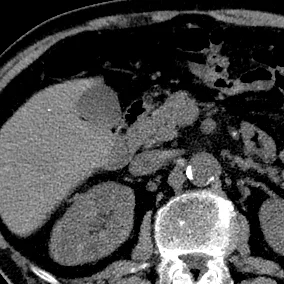

Axial image shows very subtle lesion in neck of the pancreas

61 yo M presents with weight loss and anemia, hemoglobin of 4 mg/dL. Received 2 units of blood in the ED, and routine abdominal CT shows colon mass, and incidental aortic aneurysm. Pancreas reportedly normal.

On subsequent review, a subtle nodule is visible in the neck of the pancreas adjacent to the SMV. This is much better seen on 40 keV image and iodine map. Virtual non-contrast confirms lack of calcification in nodule.